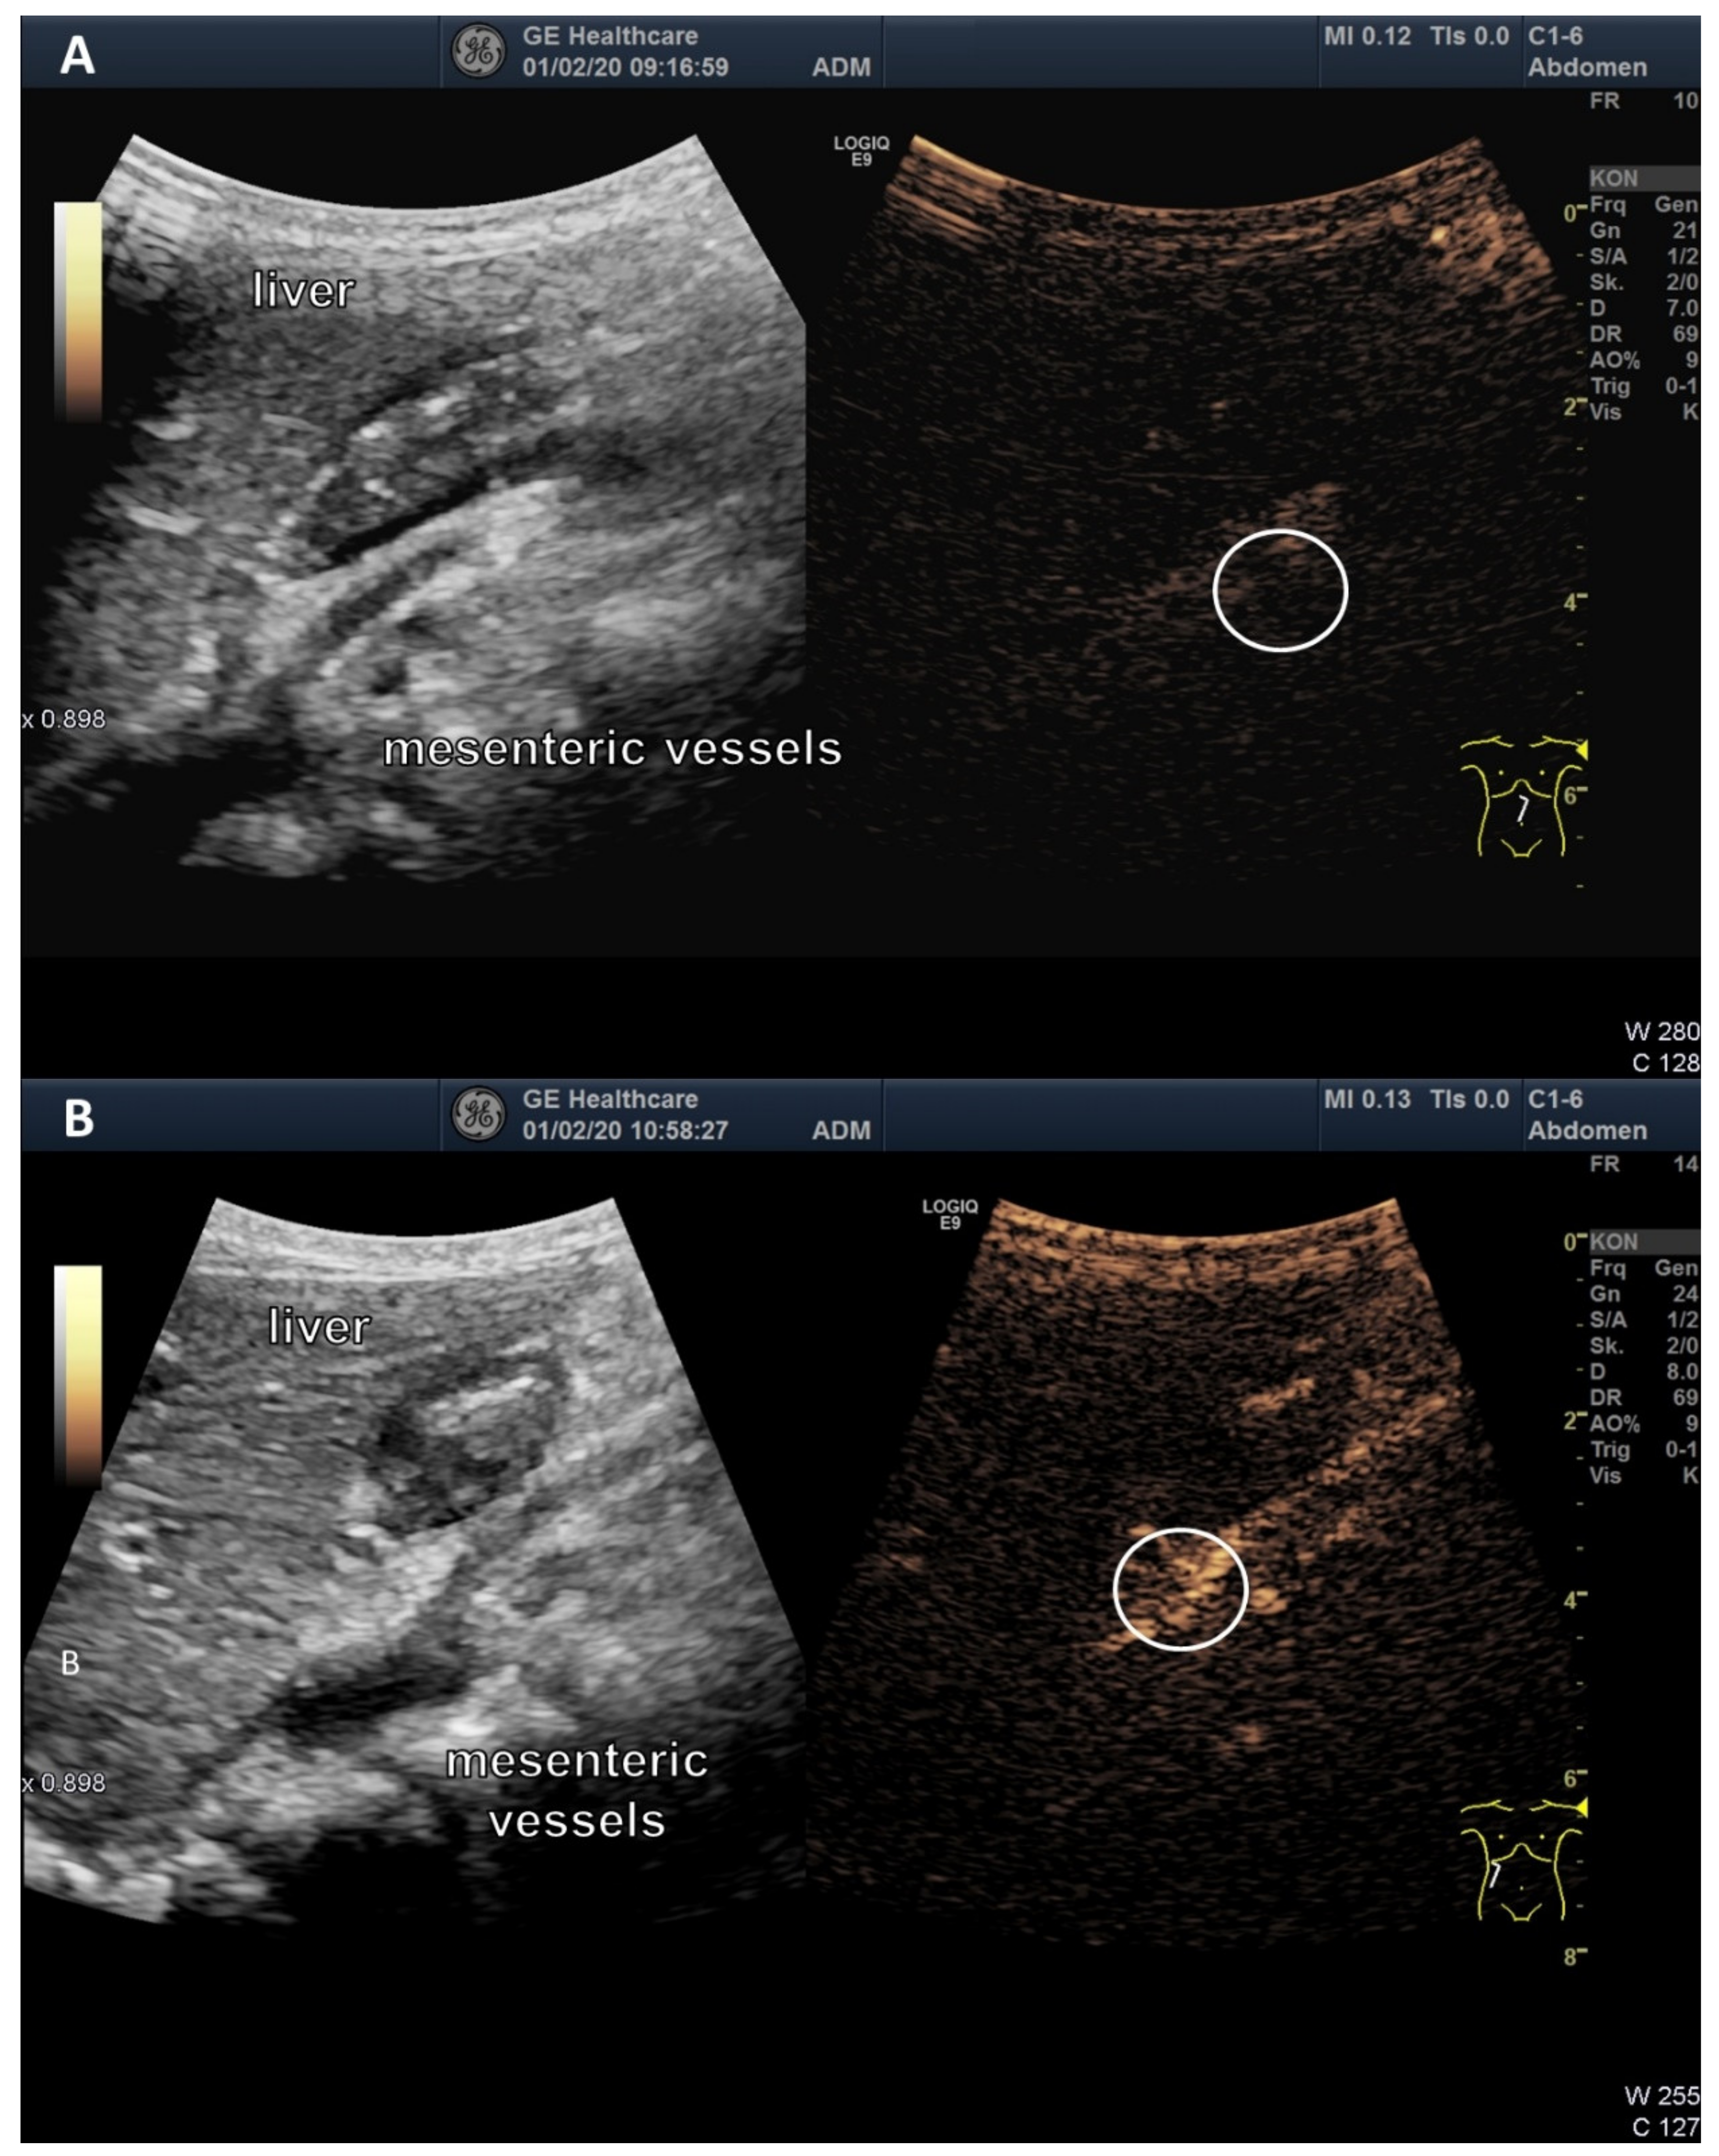

3.3. Ultrasound Examination of Intestinal Absorption